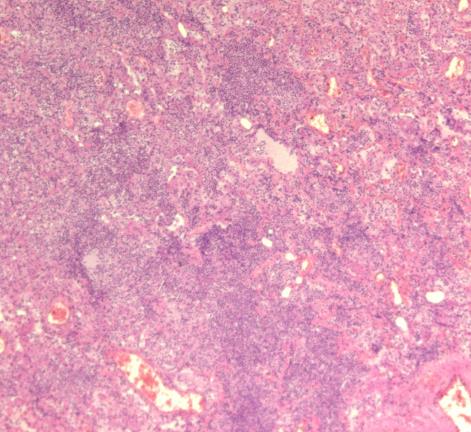

脑组织镜下情况

冠脉情况 心肌镜下情况

窦房结镜下情况

房室结镜下情况